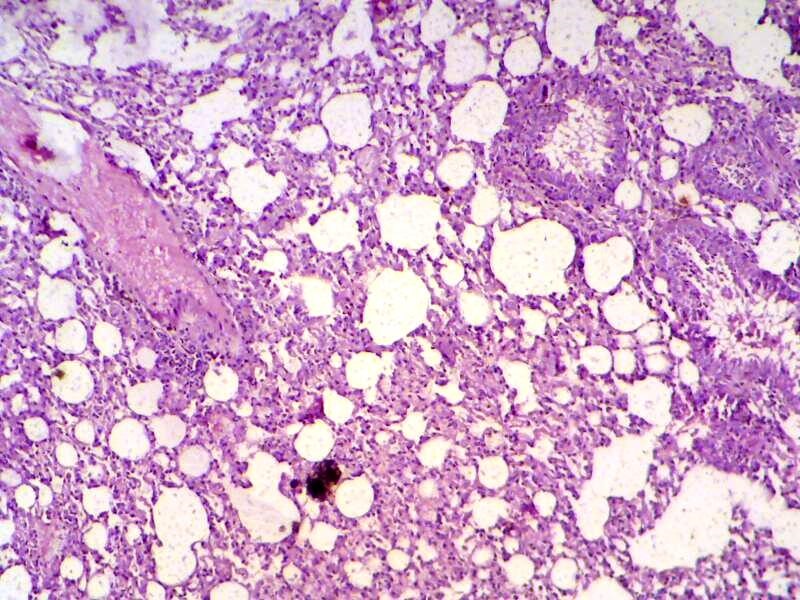

Mammary gland section shows sever inflammatory cell infiltration, haemorrhagic exudate (oedema) and destruction of adipose tissue and mammary alveoli (H&E 200 X)